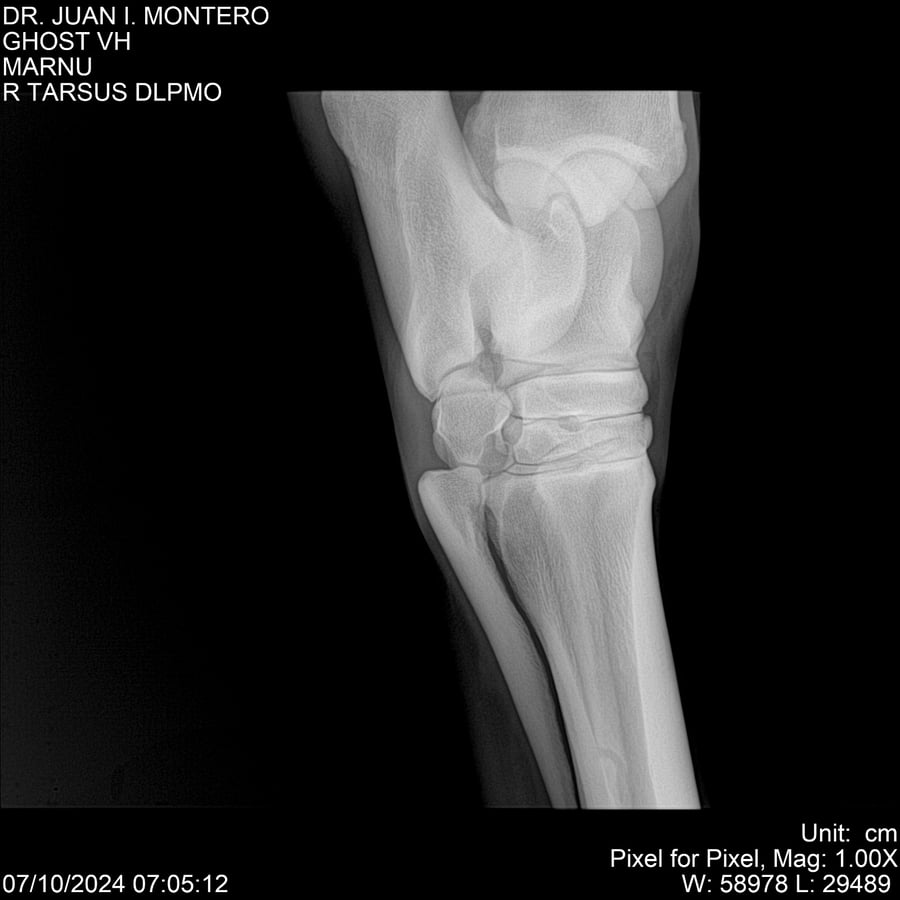

LOTE 15, GHOST VH 🔥 🔥 🔥 Lote Anterior Volver al remate Lote Siguiente Ficha Contacto Montevideo - Ficha del Lote Identificador: #282525 Categoría: Yeguarizos Montevideo - 69 Visualizaciones ClicData Contacto Empresa: Abelenda N. R., Walter Hugo Nombre*: Teléfono* : E-mail* : Mensaje Enviar Registrese gratis Este contenido Exclusivo está disponible sólo para usuarios registrados Ingresar